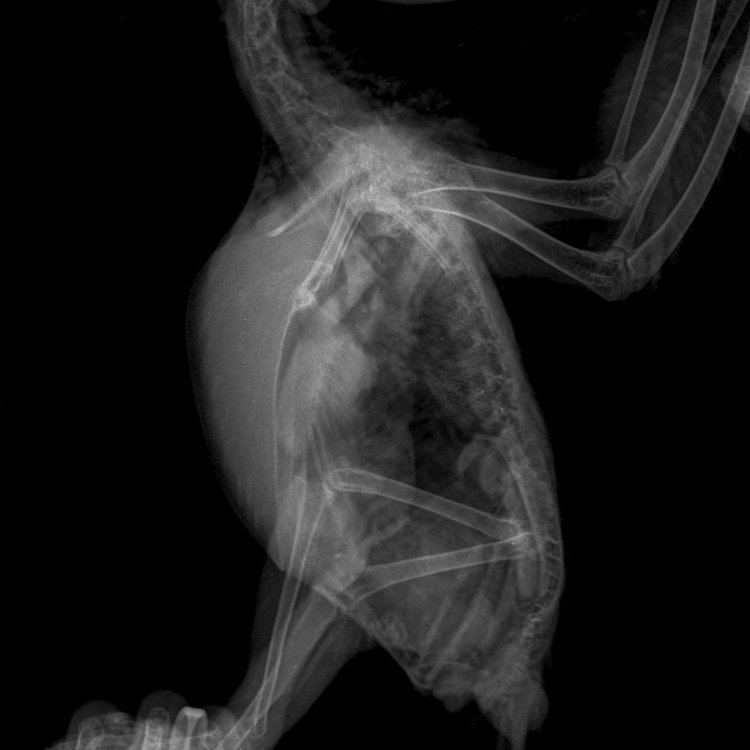

Были сегодня на приеме у врача, сделали рентген:

49550a8a-2ec7-45ef-8914-1df94ac3bfa06b384ea5-5e84-.thumb.JPE.5448ea1ec7752c165ad0122079b746cd.JPE

2137588860_6b384ea5-5e84-45ca-a26c-f60a48094715.thumb.JPE.ccd4e1350c9e68daa59d373cad1bbae2.JPE

Поставлен предварительный диагноз:

Аеросакулит.